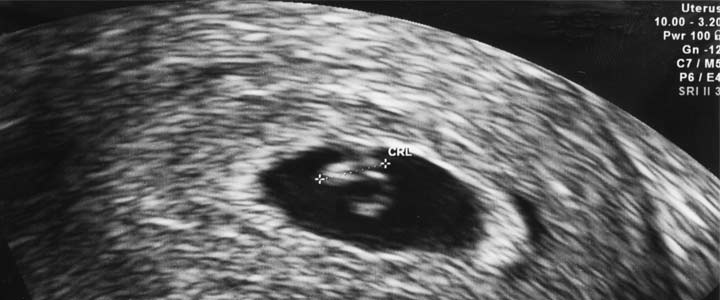

De 6-wekenecho was bij mij een inwendige echo. Soms proberen ze het ook wel uitwendig, maar meestal kunnen ze dan nog niets zien en gaan ze alsnog inwendig kijken.

Stel je niet teveel voor van de 6-weken echo. Je ziet slechts een groot zwart rondje met daarin weer een rondje wat de embryo is. Tussen de 6 en 7 weken kan je het hartje zien kloppen. Gelukkig was dat bij ons het geval (ook al was ik toen nog geen 7 weken).

Je herkent dat het hartje klopt, doorat deze wit is en flikkert. De eerste keer zal je waarschijnlijk een beetje hulp nodig hebben van de arts om het te zien, maar bij de volgende echo zal je het zelf herkennen.